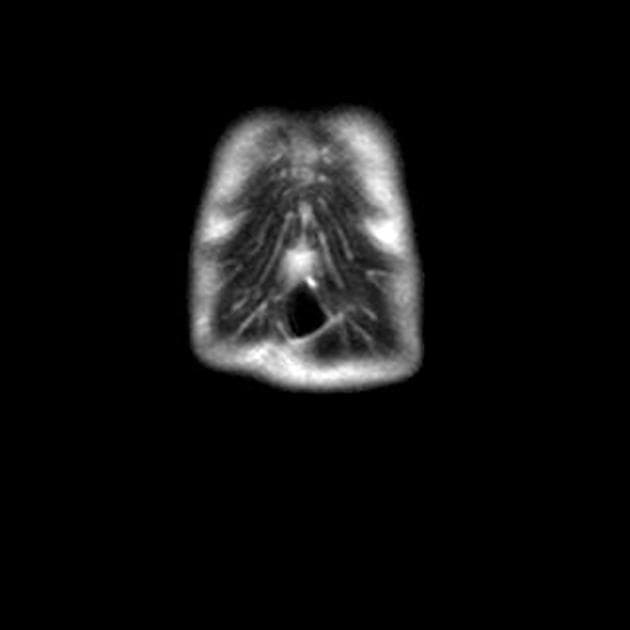

Coronal C+ portal venous phase

Ống mật chủ dãn dạng thừng, thành nhẵn, thu nhỏ dần về phía đoạn cuối.

Các nhánh mật trong gan cũng dãn.

Ống mật chủ, ống gan chung, ống gan phải và ống gan trái dãn rõ rệt.

Ống tụy hơi giãn nhẹ.

U nang ống mật chủ (choledochal cyst), khi liên quan đến tình trạng dẫn lưu bất thường giữa đường mật và tụy, có thể gây viêm tụy. Như trường hợp này, hình ảnh viêm tụy mạn tính vôi hóa (chronic calcific pancreatitis) ảnh hưởng đến quá trình móc (uncinate process) được ghi nhận.

Do trường hợp này cho thấy tình trạng dãn dạng thừng ống mật chủ, có thể phân loại là u nang ống mật chủ type I (Type I choledochal cyst), mặc dù có dãn đường mật trong gan, tình trạng này có thể do dẫn lưu bất thường giữa đường tụy và đường mật (anomalous pancreatobiliary drainage).